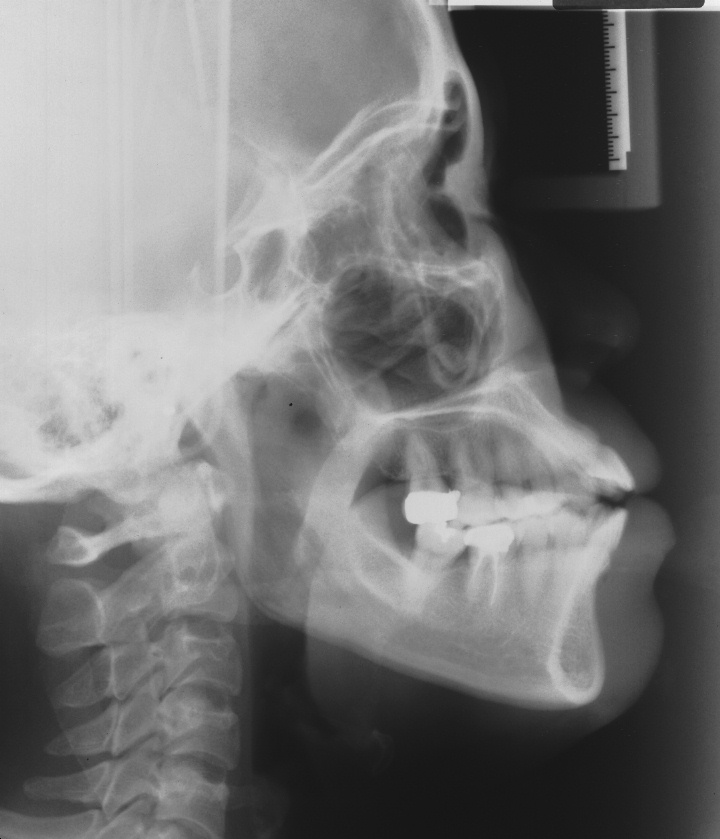

치료 후 사진입니다.